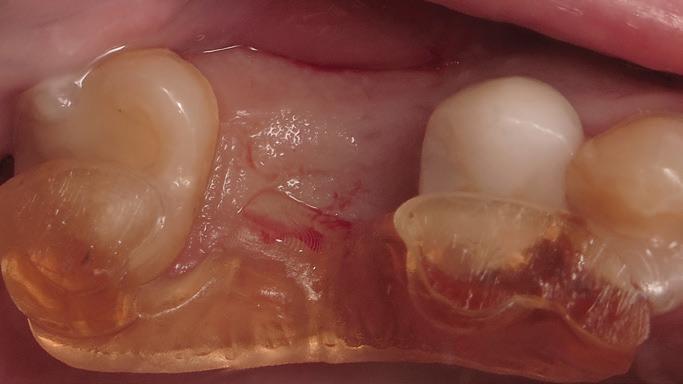

Root migration after coronectomy of impacted mandibular third molars: case reports

Gustavo Henrique de Souza Silva Enzo Balestrero

Jéssica Lemos Gulinelli

Pâmela Leticia dos Santos